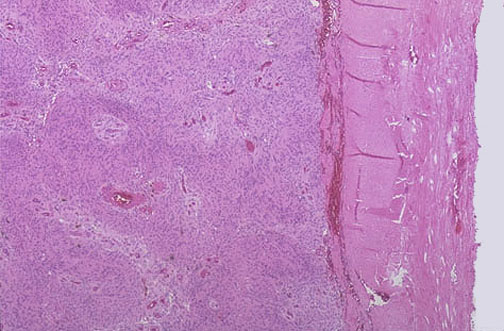

This is the microscopic appearance of a meningioma of a meningioma at low magnification. Note the dense pink connective tissue dura at the right. The cells of the meningioma have abundant pink cytoplasm.